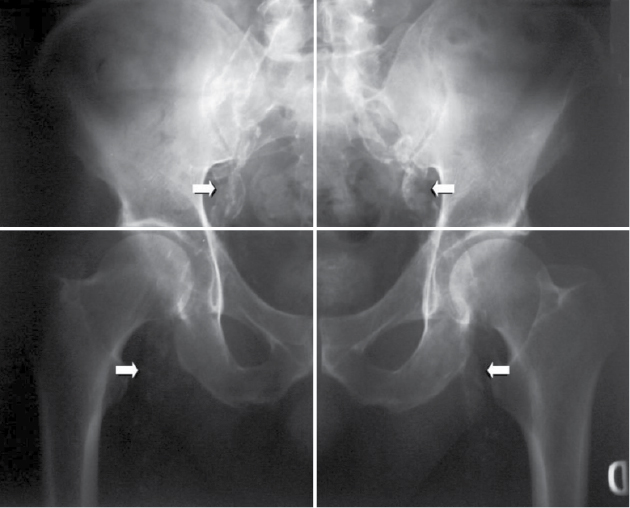

Adragao Score

This vascular calcification score was evaluated from bilateral iliac, femoral and radial arteries in plain radiographic films of pelvis and hands. The pelvis radiographic films were divided into four sections by two imaginary lines: a horizontal line over the upper limit of both femoral heads and a median vertical line over the vertebral column. The films of the hands were divided, for each hand, by a horizontal line over the upper limit of the metacarpal bones. The presence of linear calcifications in each section was counted as 1 and its absence as 0. The final score was the sum of all the sections, ranging from 0 to 8.18 Vascular calcifications were deliberately evaluated only in muscular arteries: iliac, femoral, radial and digital. Pelvic films evaluated iliac and femoral arteries (Fig. 1); wrist films evaluated radial and digital arteries (Fig. 2). Only linear calcifications, with or without patchy calcifications, were considered for the final calcification score, because they outline the vessel wall and have undoubtedly vascular localization. Patchy isolated calcifications that may be associated with intimal calcifications were not considered in this score.

Figure 1. Vascular calcification score - Pelvic films to evaluate iliac and femoral arteries.

In this study, vascular calcifications were deliberately evaluated only in muscular arteries: iliac, femoral, radial and digital, because muscular arteries are more prone to linear calcification in contrast with elastic arteries that are more prone to intimal calcification. Vascular calcification causes arterial wall stiffness,19 which results in increased cardiac afterload leading to left ventricular hypertrophy. These functional and structural changes associated with vascular calcification have strong clinical impact on cardiovascular morbidity and mortality in dialysis patients. Also, if the prevalence of both vascular calcification and CVD is high in hemodialysis patients, the association between the two observations seems logical. Indeed, several observational studies confirmed this association, suggesting linear relationship between vascular calcification and cardiovascular morbidity and mortality.14,20-22